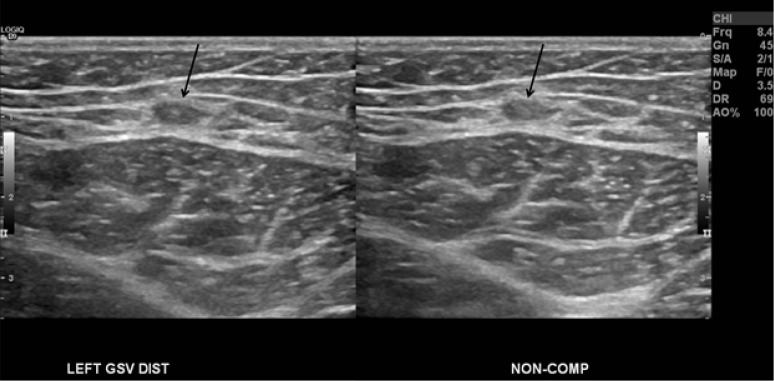

Duplex ultrasound after treatment

Duplex ultrasound is essential for monitoring of post-procedural complications and recurrence after endovenous ablation. Early post-procedure duplex ultrasound ensures satisfactory closure of ablated segments and to identify thrombotic complications. Evaluation 1–2 weeks after endovenous ablation of a treated segment will reveal smaller non-compressible veins with wall thickening and no flow (Figure 4). After several weeks, the venous wall undergoes fibrosis and become difficult to identify after several months (Figure 5).

Figure 4.

Early post-procedural evaluation with grey scale (A-C) and duplex (D) evaluation shows a non-compressible GSV with thickened walls and absent flow. GSV, great saphenous vein.